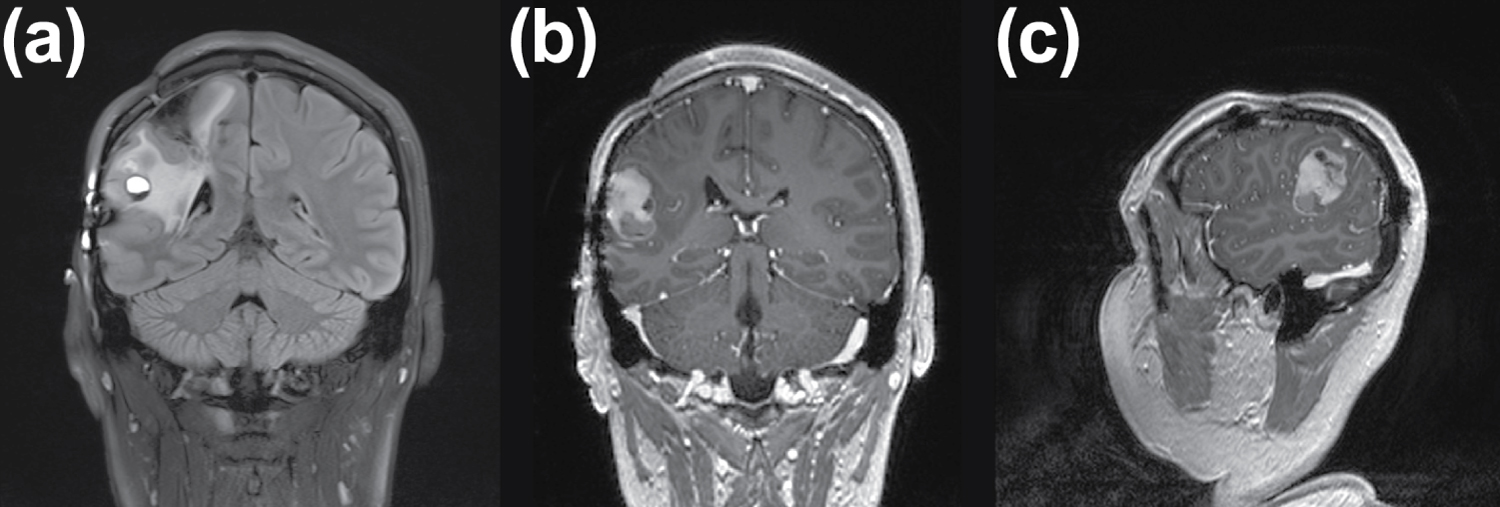

In May 2023, MRI revealed tumor recurrence involving the surgical bed, posterior insula, superior temporal gyrus, and supramarginal gyrus, measuring 4 × 4 × 4 in size, as depicted in Figure 1 and Figure 2.

Figure 2: MRI Findings, May 2023. The MRI images depict post-surgical alterations in the right parietal region, along with gliosis in the right superior parietal lobule. Notably, a mixed intra-axial lesion is evident, characterized by solid and liquid components with a level effect, measuring up to 2.5 × 3 cm in the postcentral gyrus and supramarginal gyrus. This lesion exhibits heterogeneous densities in T2/FLAIR sequences, restricted diffusion in DWI, and low values of ADC, alongside irregular contrast medium uptake and perilesional cerebral edema in the occipital horn and right atrium. Importantly, there is no displacement of cerebral structures or midline shift observed. View Figure 2